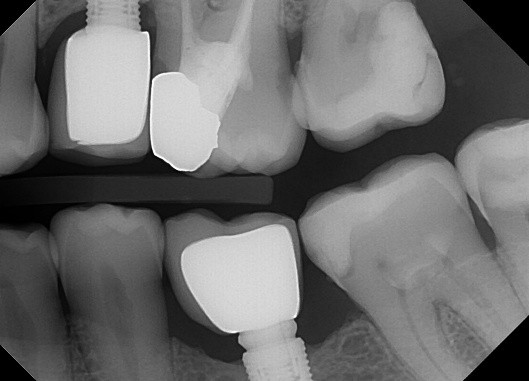

13 / 50

13. (Select ONE or MORE correct answer)

Which of the following is true regarding dental implant at site 2.6?

14 / 50

14. (Select ONE OR MORE correct answer)

Which of the following is true regarding dental implant at site 3.6?